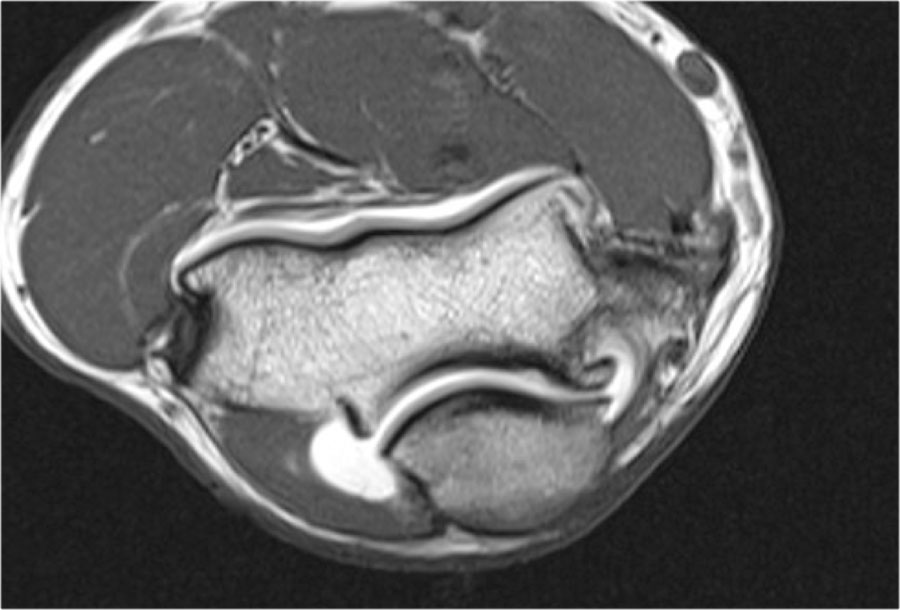

Here another case in a 20 year old gymnast.

Một lần nữa có hình ảnh thấu quang trên phim X-quang.

Hình ảnh MR-arthrogram cho thấy một số phù nề tủy xương trên mặt phẳng coronal.

Hình ảnh T1W mặt phẳng sagittal cho thấy bất thường xương dưới sụn, nhưng không có nhiều mảnh rời.

Có một số mỏng sụn, nhưng không có khuyết sụn.

Đây rõ ràng là một mảnh ổn định và không có dị vật khớp.